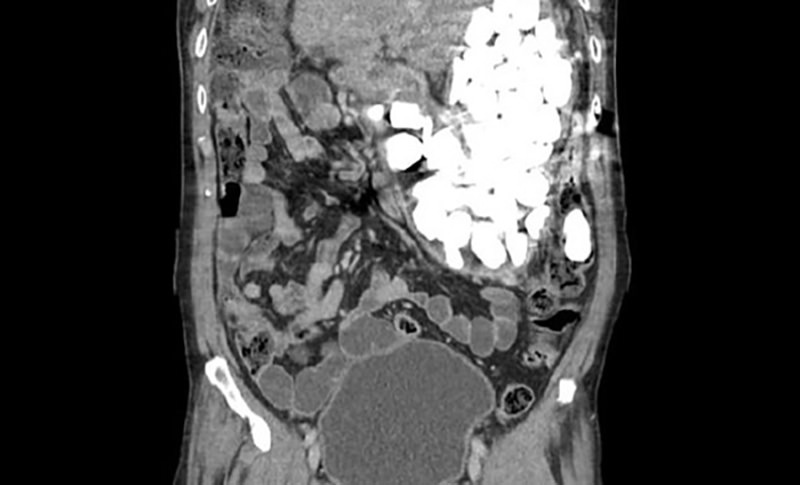

Рентген показал, что его желудок полностью заполнен инородными телами. Первоначально проглоченные предметы планировали извлечь при помощи гастроскопа, однако их оказалось слишком много. Чтобы вынуть камни, бутылочные крышки и монеты, понадобилась хирургическая операция. Мужчина провел в больнице девять дней.